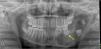

Inicialmente, se solicita una ecografía que muestra imagen quística hipoecogénica, con abombamiento cortical (fig. 1). La ortopantomografía evidencia lesión lítica que afecta a cuerpo y rama mandibular izquierdas y desplaza varios dientes (fig. 2).